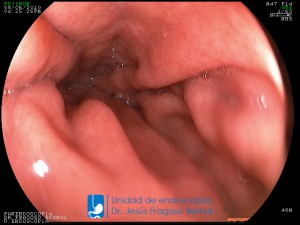

La Unidad de Endoscopía fue creada en 2002 por el Dr. Jesús Fragoso Bernal, es pionera en el estado por la utilización de la tecnología más avanzada, que nos permite ofrecer servicios integrales de diagnóstico y tratamiento para las enfermedades del aparato digestivo.

El profesionalismo de nuestro personal, altamente especializado, se distingue por la calidad y calidez de nuestros servicios con el objetivo de brindar una atención de excelencia en el ambiente más confortable para comodidad y seguridad de nuestros pacientes.

"La Unidad de Endoscopía se ha caracterizado por un progreso continuo desde su inicio marcando la pauta en los procedimientos endoscópicos en el estado de Tlaxcala y estando siempre a la vanguardia tecnológica."

Dr. Jesús Fragoso Bernal